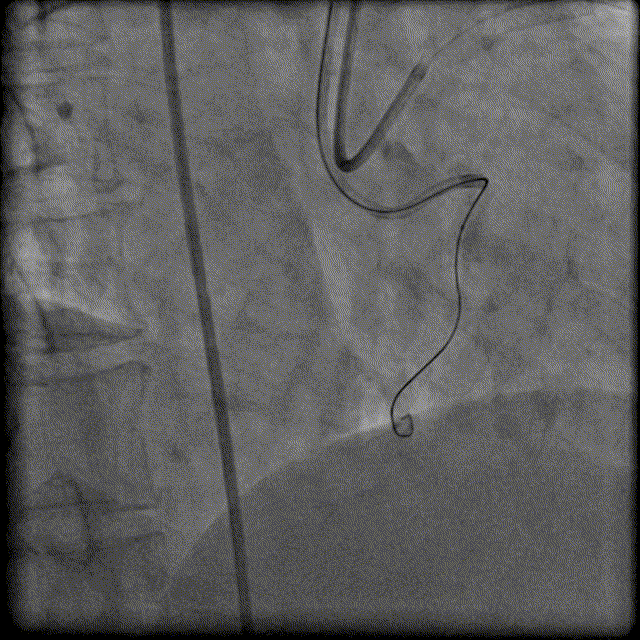

130cm Finecross微导管穿Runthrough 指引导丝到达RCA近端病变处,Fielder XTA、Pilot200指引导丝反复尝试无法通过RCA闭塞病变,随后尝试逆向侧枝开通RCA病变。

换用Instantpass微导管(170cm)支撑下送Fielder XT-R导丝通过LAD-RCA心外膜侧枝逆向通过RCA闭塞病变,推送微导管后交换Gaia Third导丝,RCA正向送Telescope™导引延长导管进行主动迎接Gaia Third导丝。